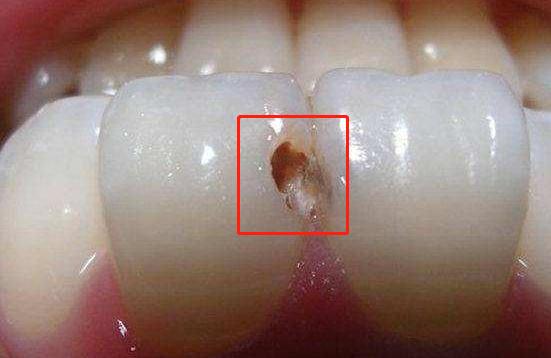

一位前来预约洁治的患者说:"最近牙齿总掉渣渣,一定是结石太多了!"可牙结石在正常情况下是不会自行脱落的,除非是堆积过多才有大块自动掉落的可能;所以后经过检查后,诊断为——牙釉质损伤,也就是我们常说的牙齿掉渣。

牙釉质形态呈现是半透明状,受损几乎很难被肉眼察觉,但是在受到冷热酸甜的刺激下会出现敏感反映,细菌持续进攻,慢慢就会形成龋齿。在不及时治疗也会容易引起牙周炎、牙髓炎、牙龈萎缩等口腔疾病。